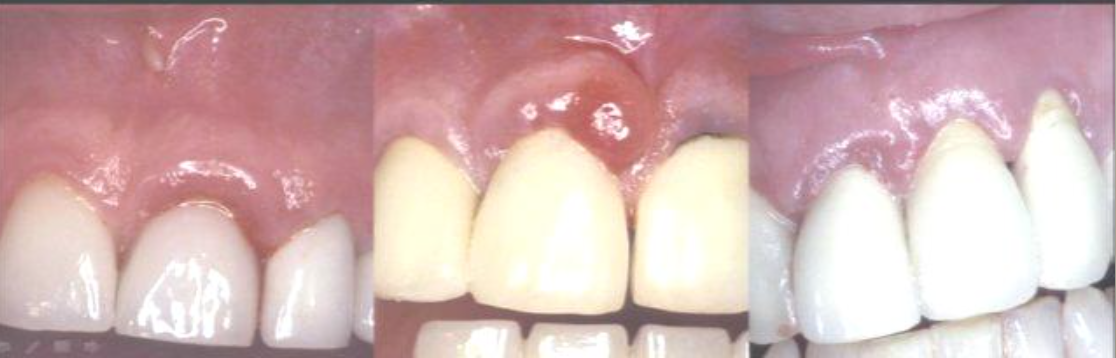

Indications for clinical crown lengthening

caries

occlusal wear

altered or delayed passive eruption

root perforation

fracture of the clinical crown

esthetics

Any factor that diminishes the dimension of the clinical crown